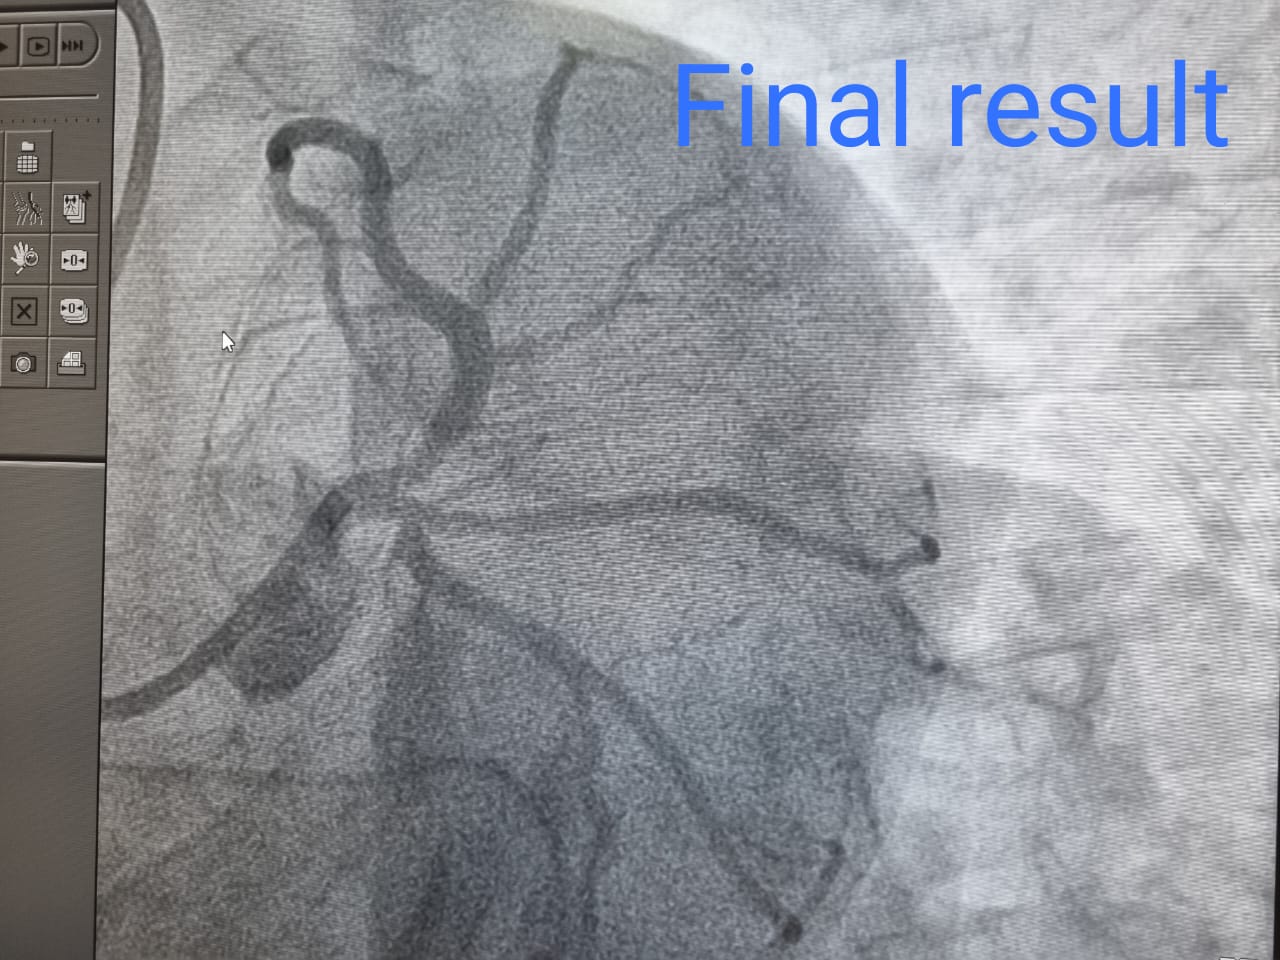

IVUS यानी हृदय की नस के अंदर की सोनोग्राफी से समझ आया कि यह रुकावट सिर्फ खून के थक्के के कारण है और इसमें नस का कोई ब्लाकेज नहीं है तो युवक की कम उम्र देखते हुए उसे खून के थक्के को लेजर द्वारा भाप बनाने का निर्णय लिया गया और यह प्रक्रिया मात्र आधे घंटे के समय में पूरी की गई और उस युवक की बंद नली पूरी तरह खुल गई और उसमें रक्त का पूरा संचार होने लगा।

इसके साथ ही हार्ट अटैक के जो ईसीजी में आए परिवर्तन थे वह भी ठीक हो गए जो इस बात के साक्ष्य हैं कि यह प्रक्रिया सफल हुई और युवक को के हृदय को और जीवन को नुकसान होने से बचा लिया गया।